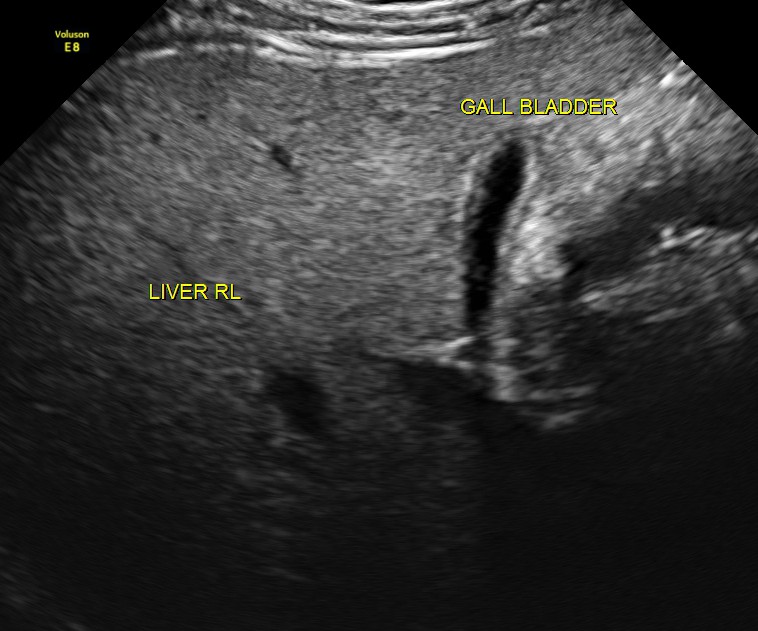

The scan was otherwise normal.